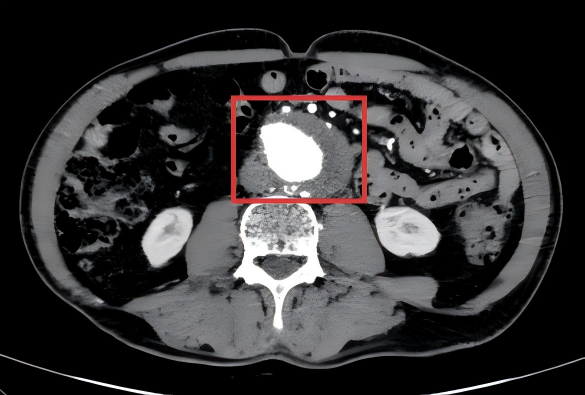

王大爷在家人的陪同下随即前往南京江北医院就诊,经动脉 CTA 检查后,明确诊断为 腹主动脉瘤样扩张伴附壁血栓形成、主动脉多发溃疡,手术指征明确,遂收入院接受治疗。

经过反复推演手术流程、模拟支架释放路径,并制定详细的围手术期管理计划(包括术前优化血压、血糖控制,术后预防感染、监测凝血功能等),团队最终确定了 「腹主动脉覆膜支架腔内隔绝术+髂动脉支架置入术」 的手术方案,简单来说,就是在血管内部植入特制的覆膜支架,像给破损的水管「打补丁」一样,精准修复了溃疡、隔绝了动脉瘤和夹层,并疏通了闭塞和狭窄的髂动脉。